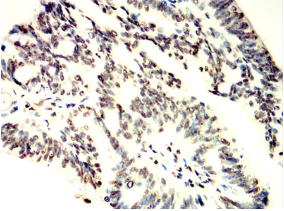

TCF7 Mouse Monoclonal antibody[1B4E9]

This gene encodes a member of the T-cell factor/lymphoid enhancer-binding factor family of high mobility group (HMG) box transcriptional activators. This gene is expressed predominantly in T-cells and plays a critical role in natural killer cell and innate lymphoid cell development. The encoded protein forms a complex with beta-catenin and activates transcription through a Wnt/beta-catenin signaling pathway. Mice with a knockout of this gene are viable and fertile, but display a block in T-lymphocyte differentiation. Alternative splicing results in multiple transcript variants. Naturally-occurring isoforms lacking the N-terminal beta-catenin interaction domain may act as dominant negative regulators of Wnt signaling.

Immunogen:    Purified recombinant fragment of human TCF7 (AA: 168-358) expressed in E. Coli.

IHC    1/200 - 1/1000